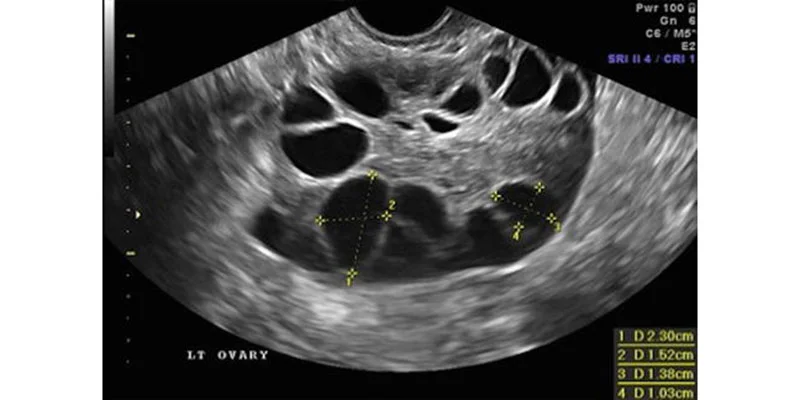

1. Follicular Study

A follicular study is a specialized ultrasound used to monitor ovulation during natural cycles or fertility treatments.

• Track follicle growth in the ovaries